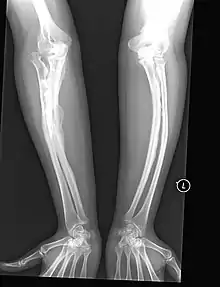

The most direct example of the role of Sp7 in human disease has been in recessive osteogenesis imperfecta(OI), which is a type-I collagen related disease that causes a heterogeneous set of bone-related symptoms which can range from mild to very severe. Generally this disease is caused by mutations in Col1a1 or Col1a2 which are regulators of collagen growth. OI-causing mutations in these collagen genes are generally heritable in an autosomal-dominant fashion. However, there has been a recent case of a patient with recessive OI with a documented frameshift mutation in Sp7/Osx as the etiological origin of the disease.[11] This patient displayed abnormal fracturing of the bones after relatively minor injuries and markedly delayed motor milestones, requiring assistance to stand at age 6 and was unable to walk at age 8 due to pronounced bowing of the arms and legs. This provides a direct link between the Sp7 gene and the OI disease phenotype.